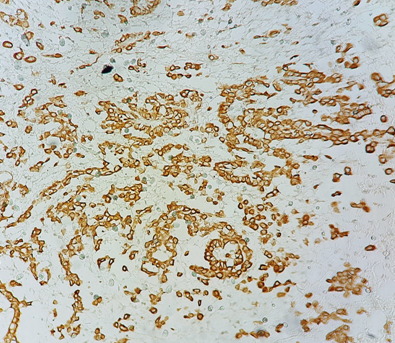

Figure 3 Immunohistochemical study: Diffuse labeling of tumor cells by anti-calretinin antibody (pathology department of CHU Hassan II in Fez).a

The immunohistochemical study is essential for the diagnosis of MPM, especially for differential diagnosis. The 3 most used positive markers are CK 5/6, calretinin and WT1. In our study, the epithelioid form was found in a single patient. For the rest of the patients, the complete pathological study could not be performed due to the small size of the samples.